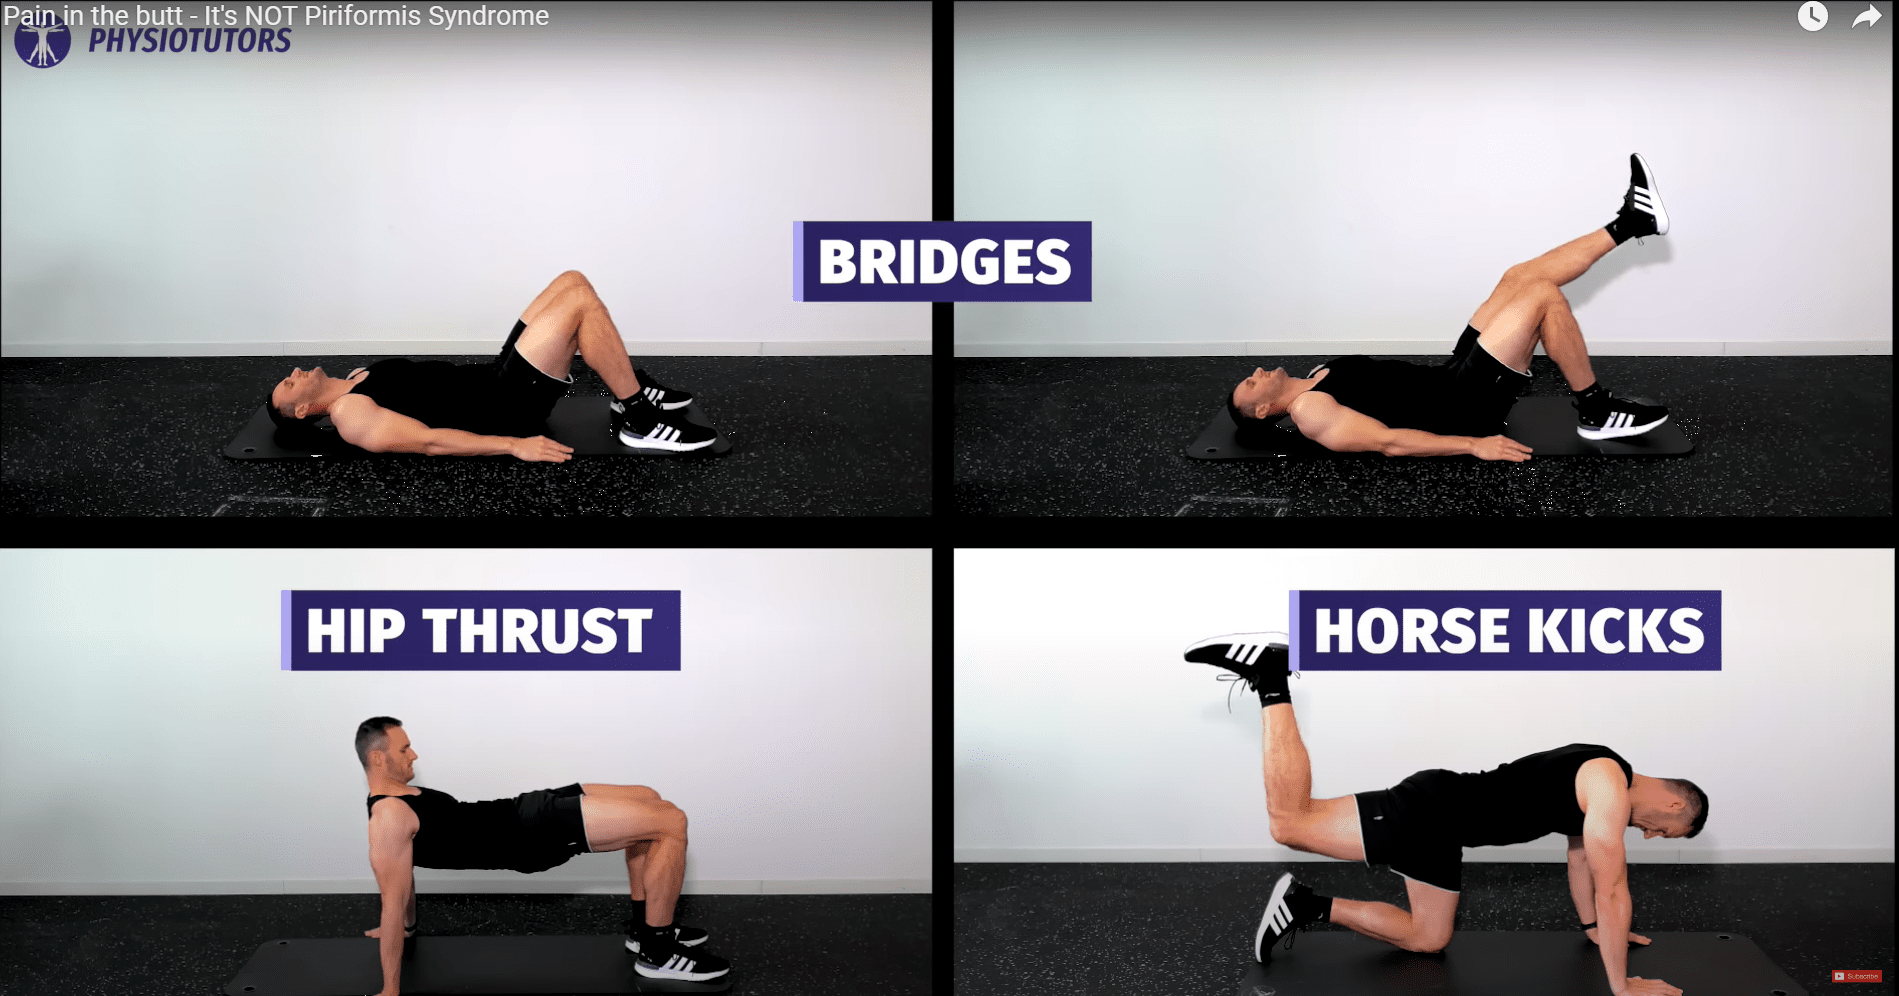

Här är ett exempel på ett progressivt träningsprogram med början från enkla till mer avancerade övningar:

- Clam Shells 🡪 Lägg till motståndsband 🡪 sidoplanka clamshell

- Brandposter i sittande 🡪 fyrfota🡪 stående med motståndsband

- Glute broar 🡪 1 ben

- Sparkar från häst

Om dessa övningar är acceptabla kan du gå vidare till tyngre och mer globala övningar, t.ex.